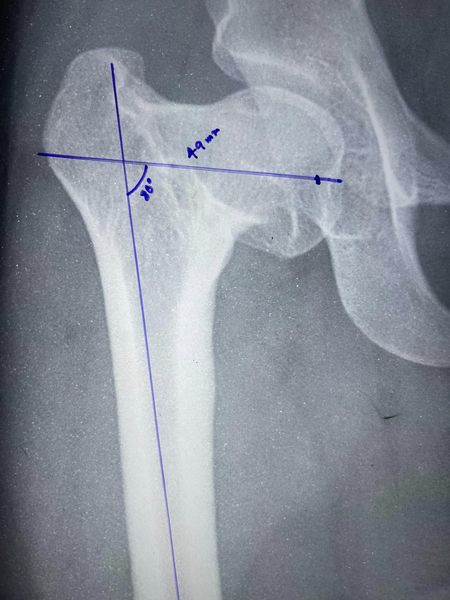

Interesting fact: We usually do pre-operative planning and measurements in such cases, the neck length when measured came to 49mm and 50 mm is the shortest screw I could find after calls to all companies who supply such screws in and around Kolkata. Very close call no?